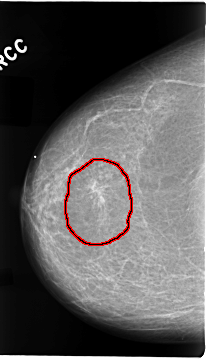

FILE: C_0073_1.RIGHT_CC.OVERLAY

TOTAL_ABNORMALITIES 1

ABNORMALITY 1

LESION_TYPE MASS SHAPE ARCHITECTURAL_DISTORTION MARGINS SPICULATED

ASSESSMENT 4

SUBTLETY 5

PATHOLOGY MALIGNANT

TOTAL_OUTLINES 1

BOUNDARY